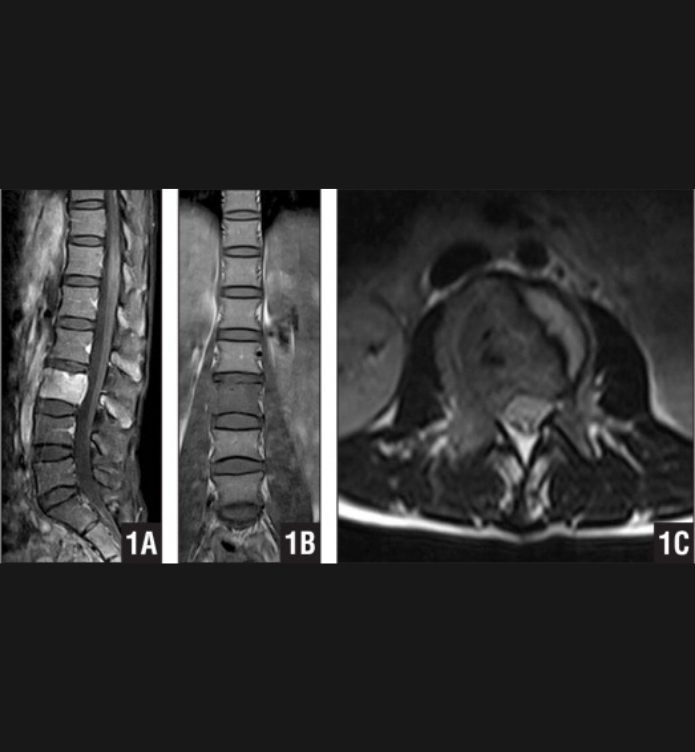

Basit Omurga ve Omurilik Anatomisi Omurga, 33 adet omur kemiğinden oluşur. Bu kemiklerin 7 tanesi boyun omuru, 12 tanesi sırt omuru, 5 tanesi bel omurudur. Beş tanesi birleşmiş olarak sakrum denilen kemiği ve 4 tanesi yine birleşmiş olarak koksiks denilen kuyruk sokumu kemiğini oluşturur. Omurganın görevi omuriliği korumak ve gövdeyi dik pozisyonda tutmak için destek […]